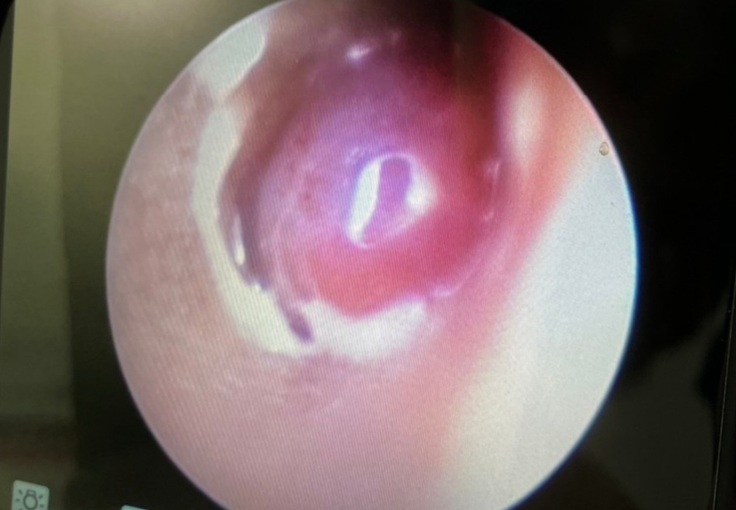

【ぎん君】は8日に予定通りCTと肉腫の切除の手術になりました。

耳の中を見ると大きな出来物?が見受けられたとのことで肉腫なのか異物なのかを確認してから、焼きながら切除とのことでした。

傾きやよろけがあることから内耳や中耳にも何らかの異常があるとして、外耳よりも内耳や中耳の様子の確認がメインになるとおっしゃって、内耳や中耳に異常の度合いにより内科的な処置、もしくは外科的な処置をしていくか判断するとして手術に入られました。

手術の結果としては外耳に腫瘍がありそちらを少しずつ取り除いていただきました。

一枚目は手術前、2枚目は切除あと。

ただ問題は鼓膜近くの見えている外耳の腫瘍ではなく、その先。つまり鼓膜の中、中耳の鼓室から腫瘍が派生していると思われるとのこと。

鼓膜を破っての腫瘍の派生とのこと。

幸いこの腫瘍は良性が多いということですが確認の為、病理検査に出すことになりました。